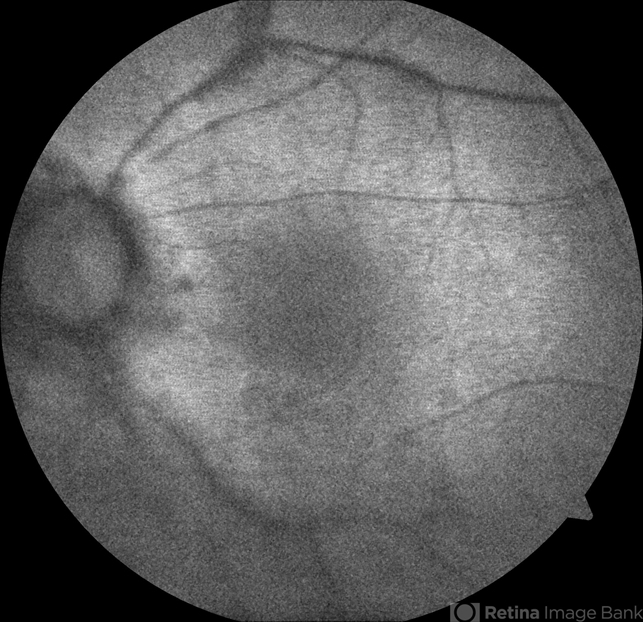

- birdshot, birdshot retinochoroidopathy, birdshot chorioretinopathy

- 64-year-old Puerto Rican woman consulted due to the presence of 1+ vitreous cells. The fundus examination revealed orange to yellow lesions dispersing from the disk. Work-up revealed she was HLA-A29 positive and the suspected diagnosis of Birdshot Chorioretinopathy was made. Chest X-Ray, FTA-Abs and RPR were negative.